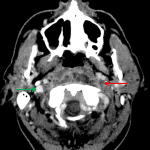

- Mass effect on the left internal jugular vein with occlusive thrombus in the left internal jugular vein extending cranially from the level of C1-C2 into the imaged portions of the left sigmoid and transverse sinsuses

Associated compression of the left internal jugular vein with occlusive thrombus extending cranially from the level of C1-C2 into the visualized portions of the left sigmoid and transverse sinuses. Recommend brain MRI with and without contrast for further assessment.